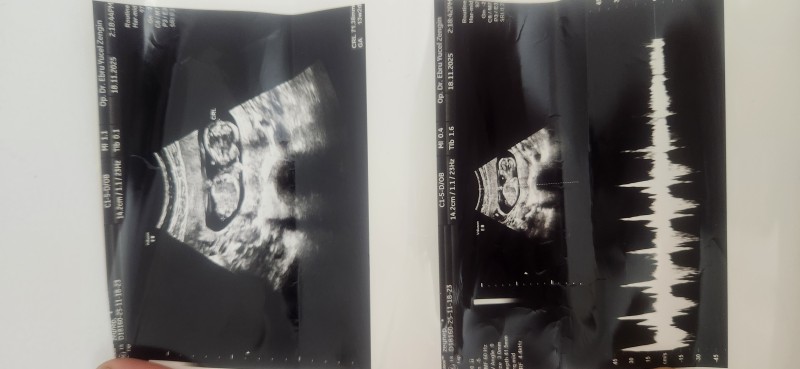

Dün hastaneye gittim doktor kendini göstermiyor dedi

image

Devlete gidiyorsan klişedir, göstermiyor derler. Şu görüntüde bir fetüsün cinsiyeti görünür de seçilir de.